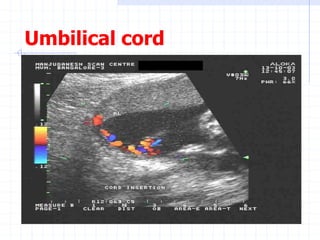

Umbilical Doppler Velocimetry

Any high risk pregnancy

Use a free loop of umbilical cord to

Umbilical cord